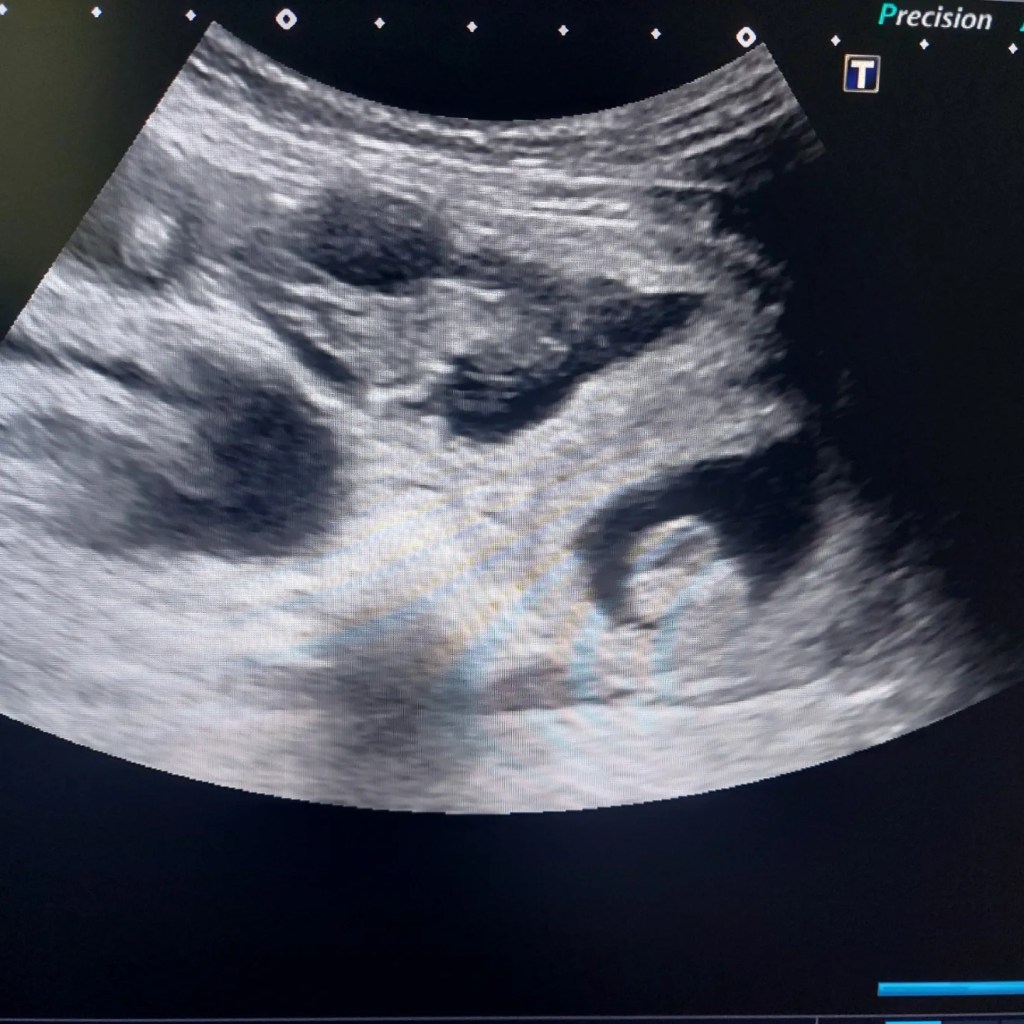

Meille on tulossa pentuja!

Meille on tulossa pentuja! Ensimmäistä kertaa kymmeneen vuoteen on Lifedream kenneliin syntymässä uusia elämänunelmia elokuun alussa.…